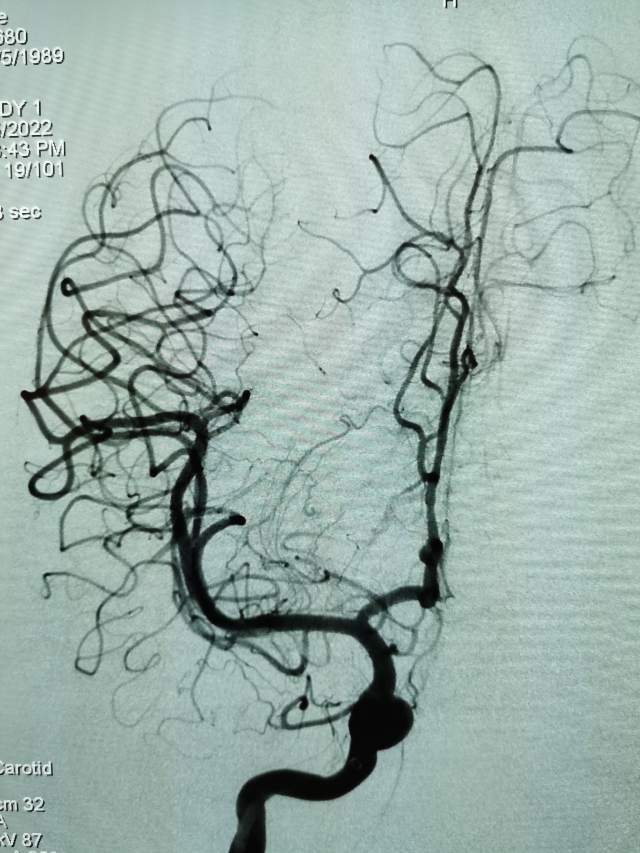

第一次手术:我们先超选6个分支小血管给予栓塞,去其枝叶,保留主干,结构逐步显山露水,清晰可见引流静脉的起始部,为二期手术做足准备~~~